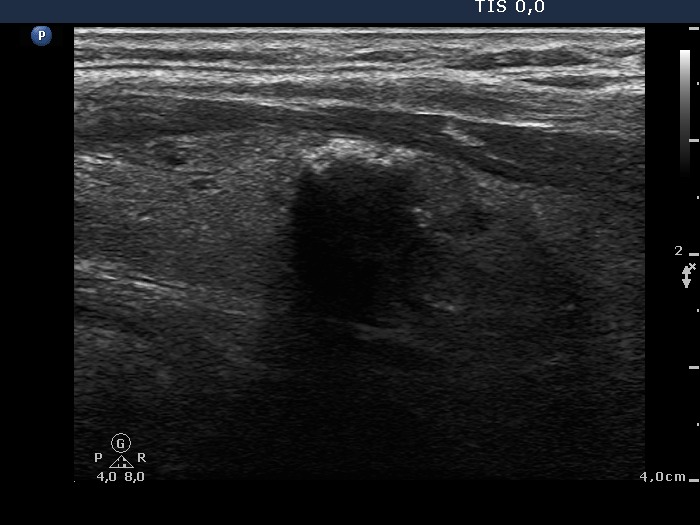

Benign hyperplastic nodule (histological diagnosis) - case 80

There were multiple foci of coarse calcification in this case. Note that acoustic shadowing is complete only at the edges of the lesions.